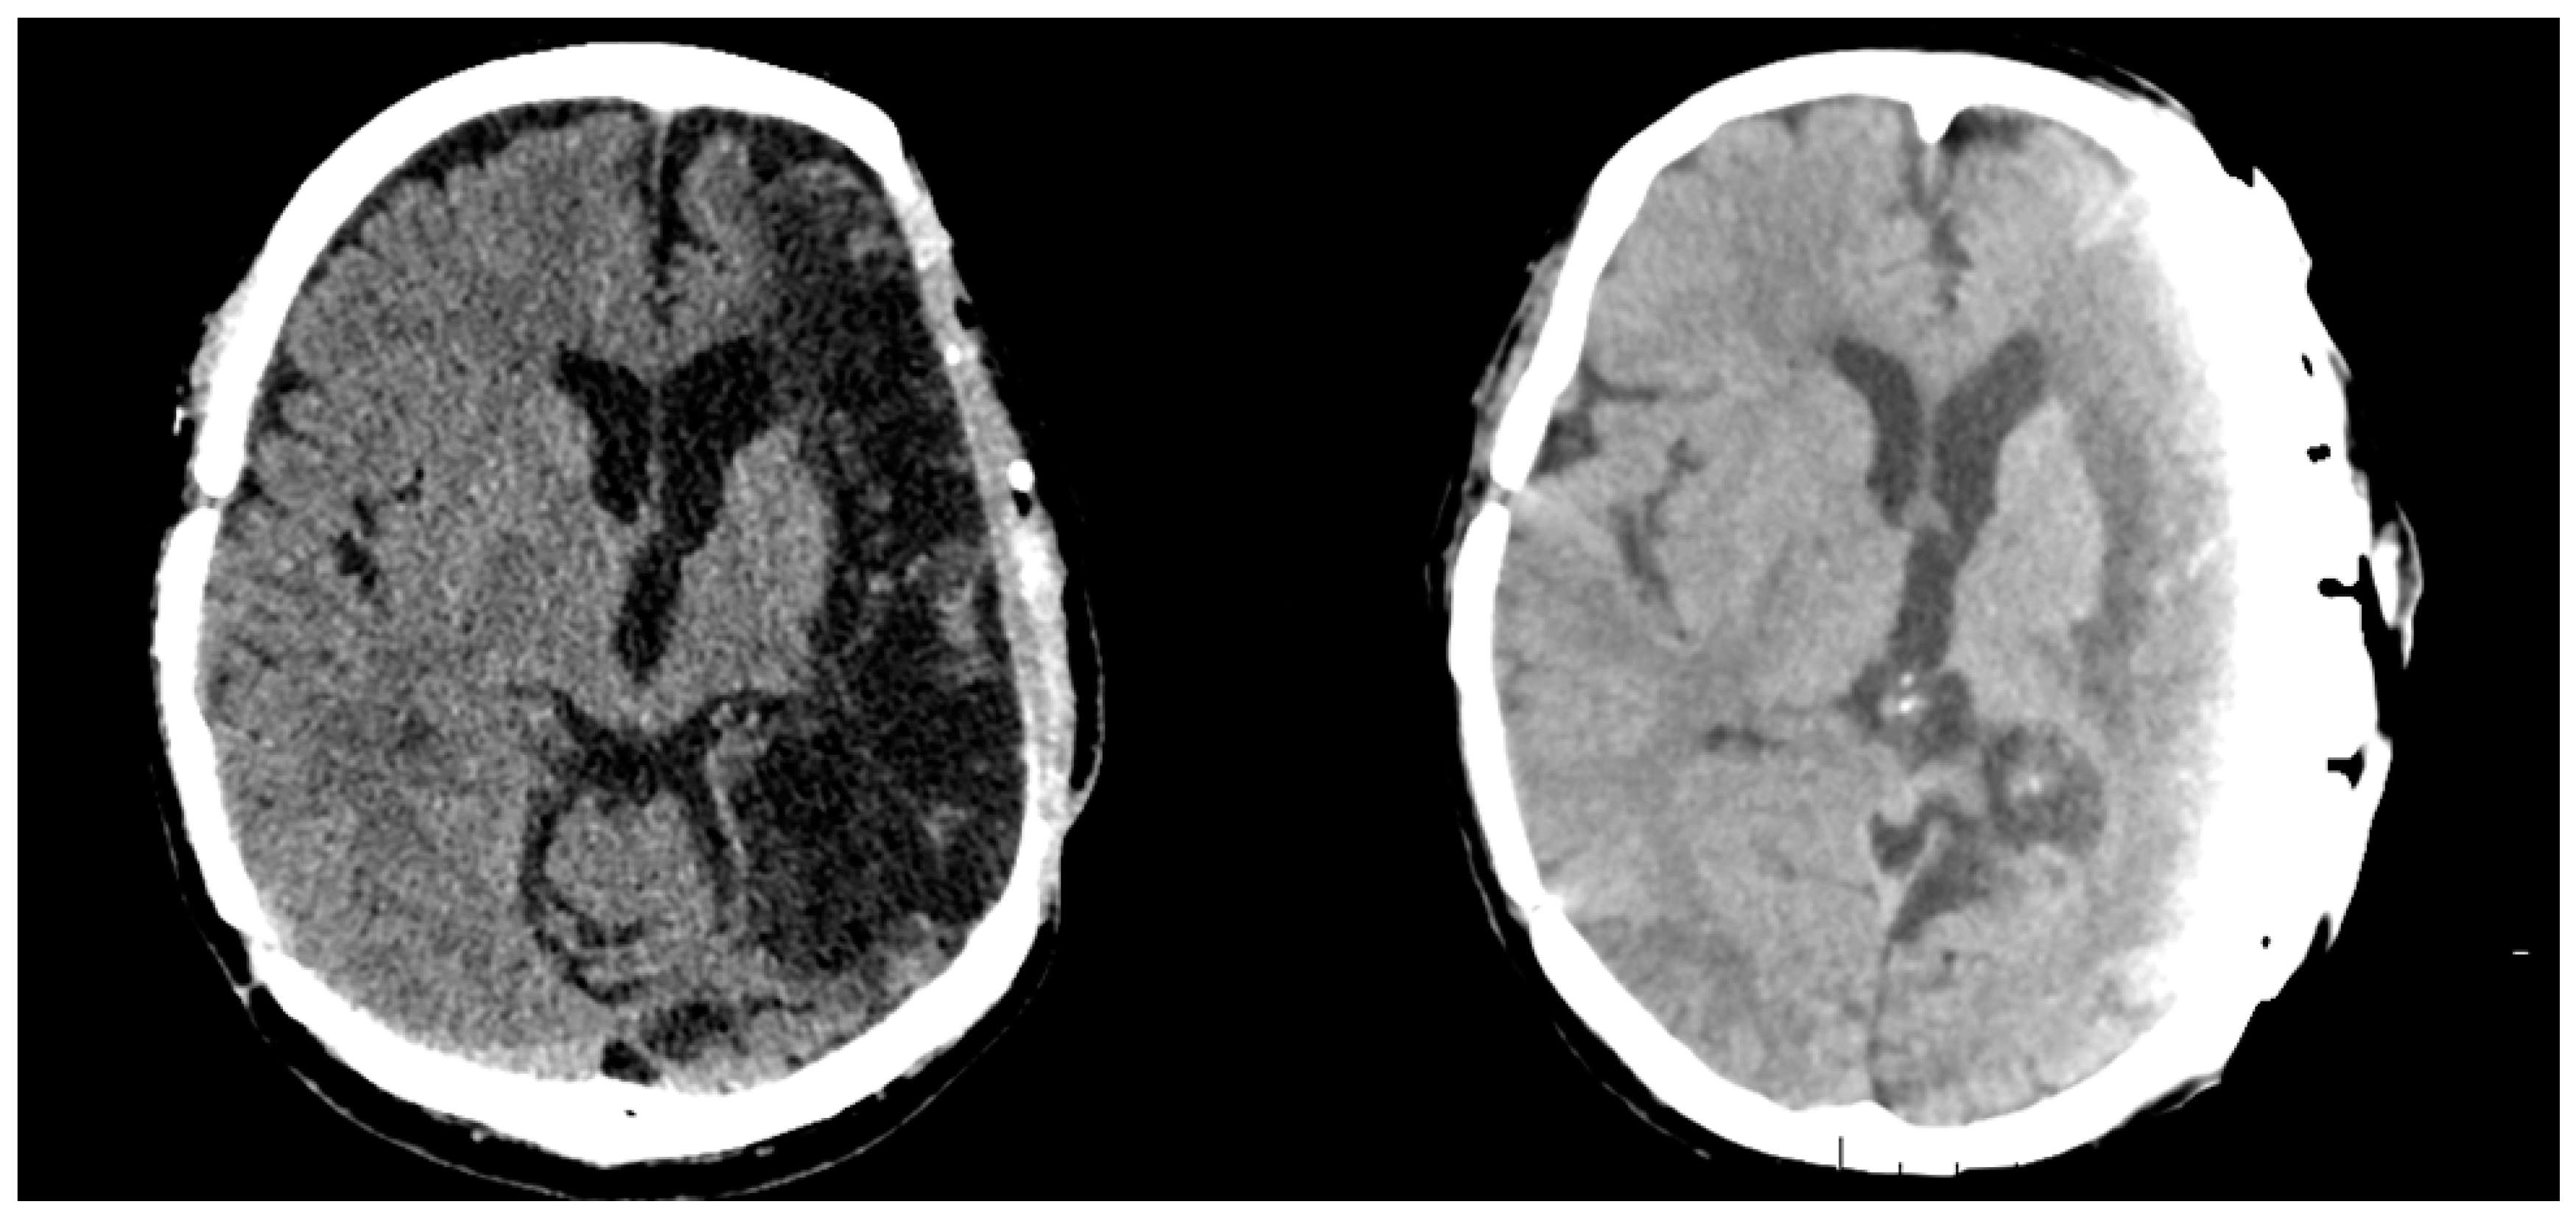

2. Case Report